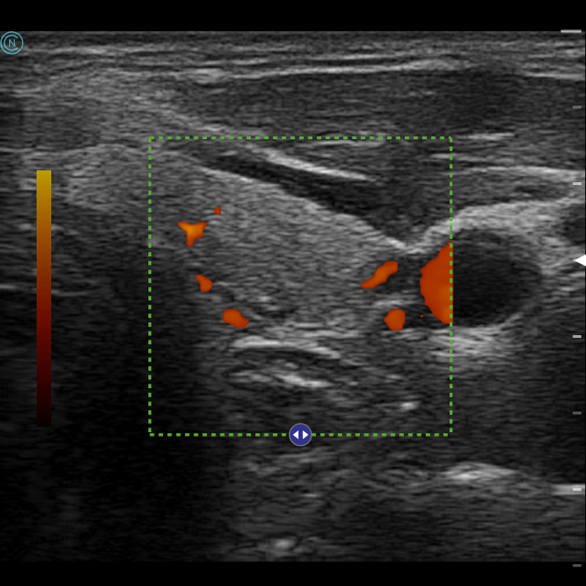

- 甲狀腺與副甲狀腺檢查:快速檢測結節大小與性質,並協助追蹤變化。

- 頸部淋巴結掃描:辨別是否為發炎或惡性腫瘤轉移。

- 唾液腺病變:檢查是否有結石、腫瘤或囊腫。